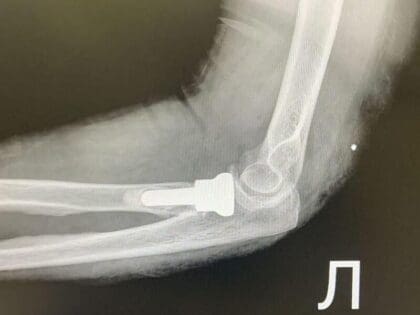

Протезирование головки лучевой кости помогло двум пациентам восстановить подвижность руки. Рассказываем, когда нужна такая операция.